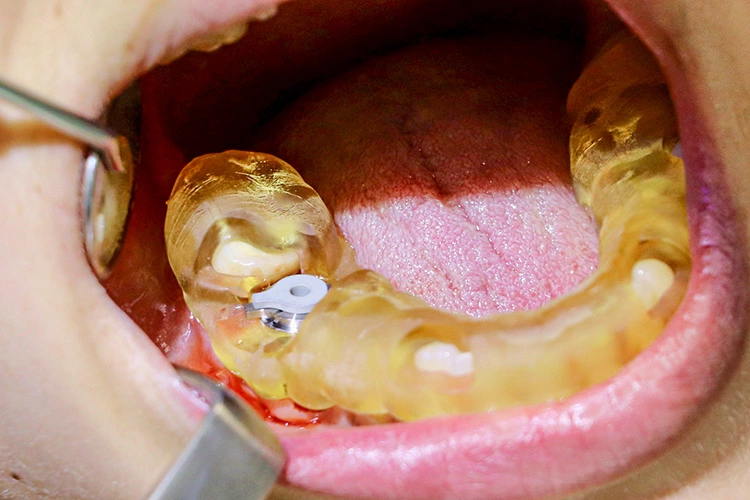

Die Dokumentation des Implantatsitzes erfolgte mit einer postoperativen Panoramaschichtaufnahme (Abb. 16). Nach der gedeckten Einheilung erfolgte im Juni 2021 die geschlossene Implantatabformung mit Impregum. Abbildung 17 bis 25 zeigt den Ablauf von der Inzision drei Monate nach Implantation bis zum Einsetzen des Hybrid-Abutments mit Titan-Klebebasis und Zirkonaufbau bis zur finalen Zirkonkrone, die aufgrund einer Erkrankung der Patientin etwas später als vorgesehen im Juli 2021 eingegliedert werden konnte. Die Versorgung der insuffizienten Einzelkrone 47 erfolgt auf Patientenwunsch zu einem späteren Zeitpunkt.